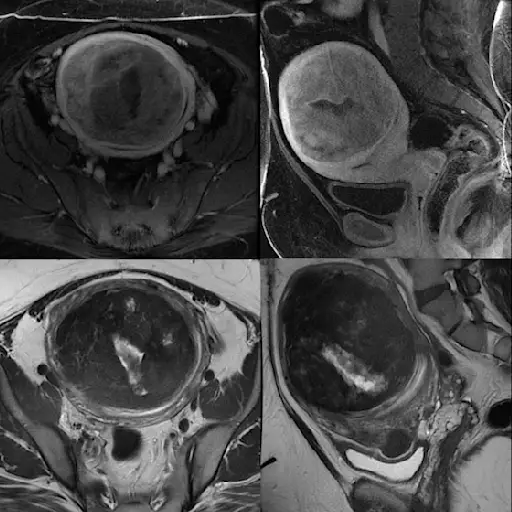

如果你喜欢我们很多人,子宫肌瘤不是你花了很多时间的想法。但是,如果你是一个女人接近她生育的岁月的结束,你可能已经经历过UF(即使你不知道它)。这些非癌症,通常是无症状的生长通常在30多岁和40岁的女性中出现,而你达到了5-0的时间,估计有80%的女性已经开发了至少一个。这些生长的确切原因(范围小于鹅卵石到葡萄柚)是未知的,但有一些理论。我们向专家询问了底线。

无论病因如何,大多数女性甚至不知道自己有子宫肌瘤,只有30%的子宫肌瘤足够大,可以在盆腔检查中发现。如果你被诊断为UF,“一定要向你的医生/医疗服务提供者询问适合你情况的肌瘤治疗方案,”Breitkopf医生说。“在过去,手术是唯一的选择。现在有很多新的有效治疗方法可以让患者更快地恢复正常活动,”他补充道。